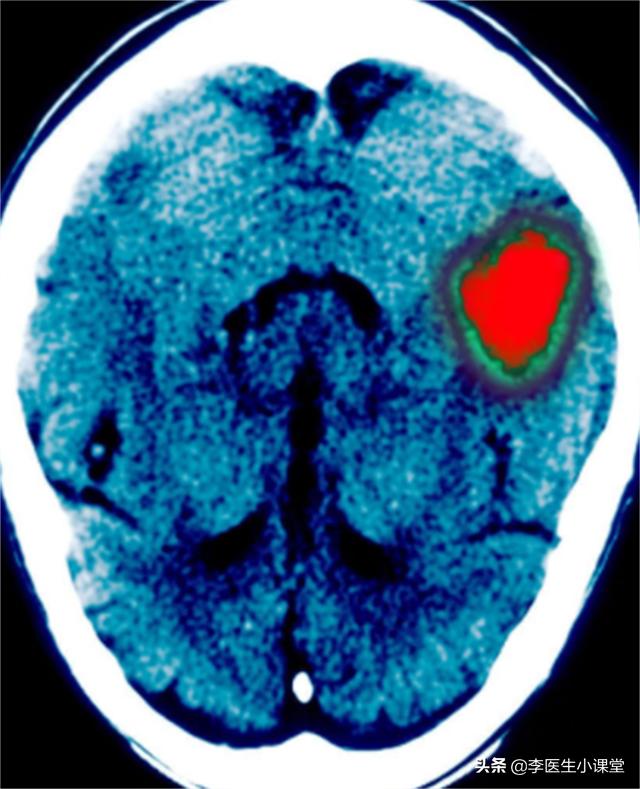

患者体温36.7℃、血压160/100、身高174cm、体重75kg。患者入院时意识模糊,无法正常沟通。颅脑CT显示:左侧基底节区脑出血(约15ml),双侧基底节区软化灶形成,可确诊为急性脑出血。